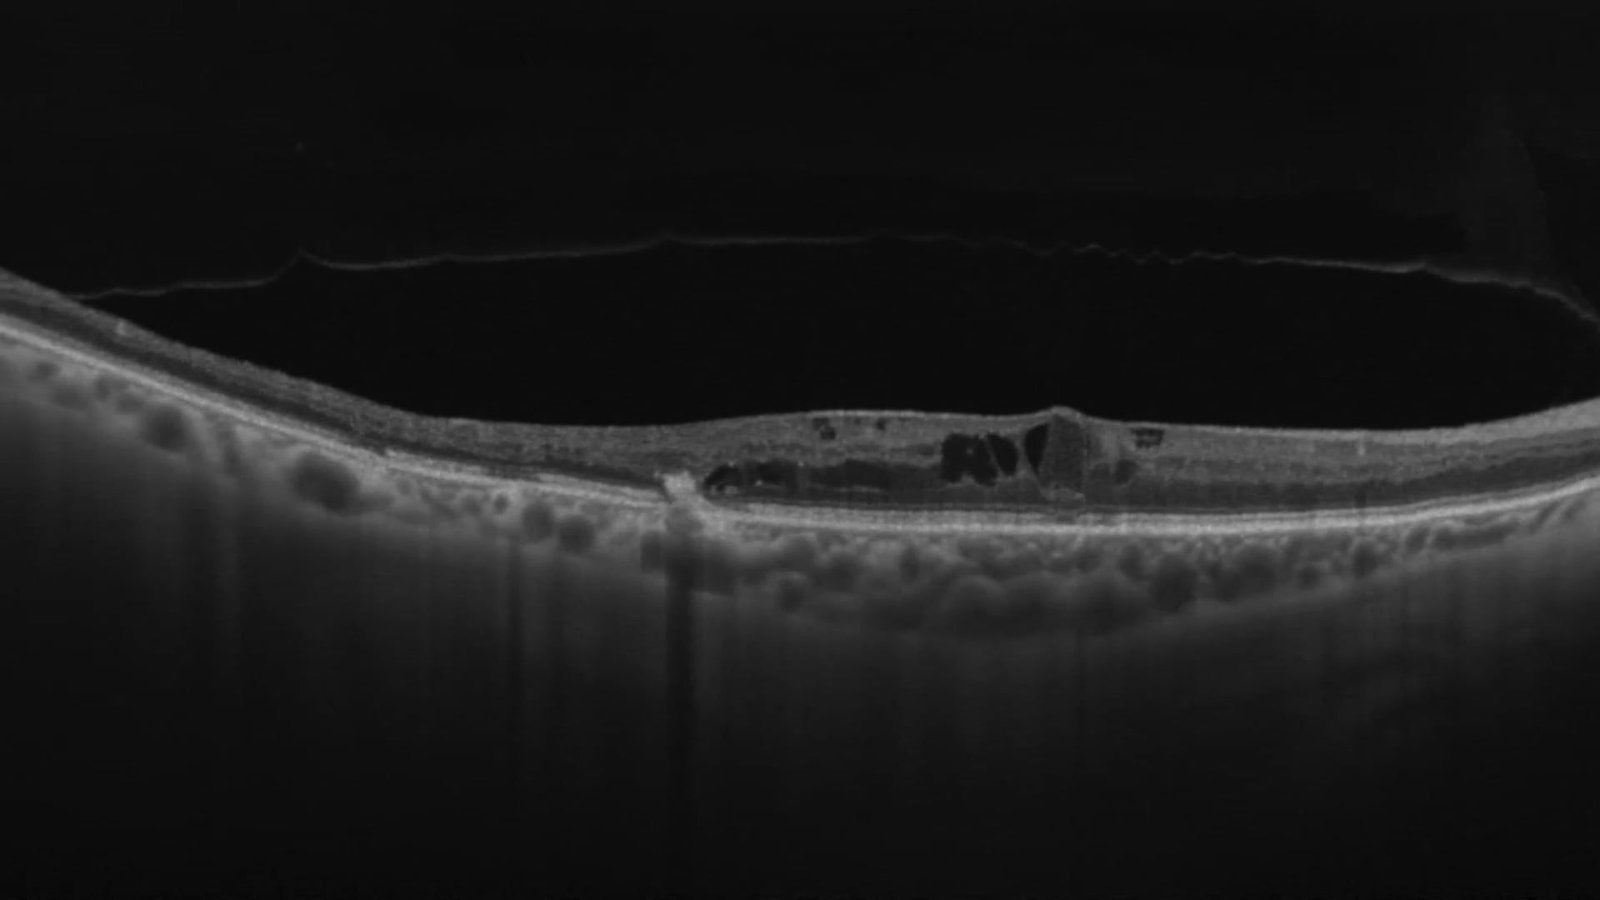

Desprendimiento de Descemet

Fernando Aguilera